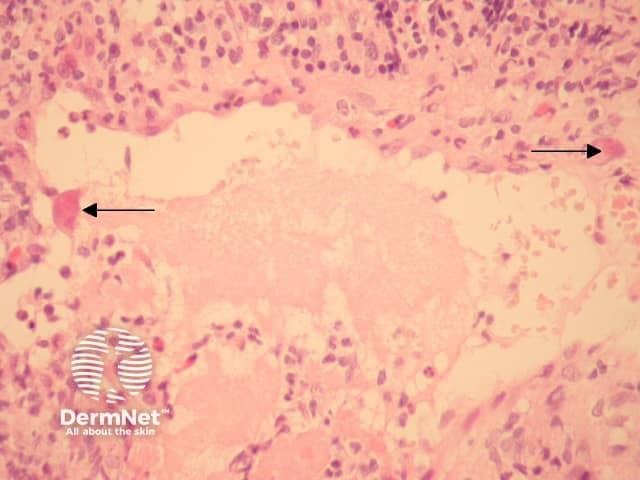

Cytomegalovirus (CMV) is a member of the family Herpesviridae. In cutaneous cytomegalovirus infection, markedly enlarged endothelial cells are seen lining small vessels (Figure 1, arrows). These are larger and eosinophilic when compared with normal or reactive endothelial cells. The hallmark histologic feature is a large intranuclear inclusion which is densely eosinophilic (Figure 2, arrow). Other cells such as fibroblasts and epithelial cells are less commonly involved.

The inclusions may be seen in the context of overlying epidermal ulceration and other non-specific inflammatory changes. Leukocytoclastic vasculitis is a described reaction pattern.

Reactive changes — reactive endothelial cells can become enlarged and hyperchromatic. Dense eosinophilia (Figure 1) and the classic intranuclear inclusions (Figure 2) are not seen as a reactive phenomenon. Immunohistochemistry can be useful if needed (Figure 3).